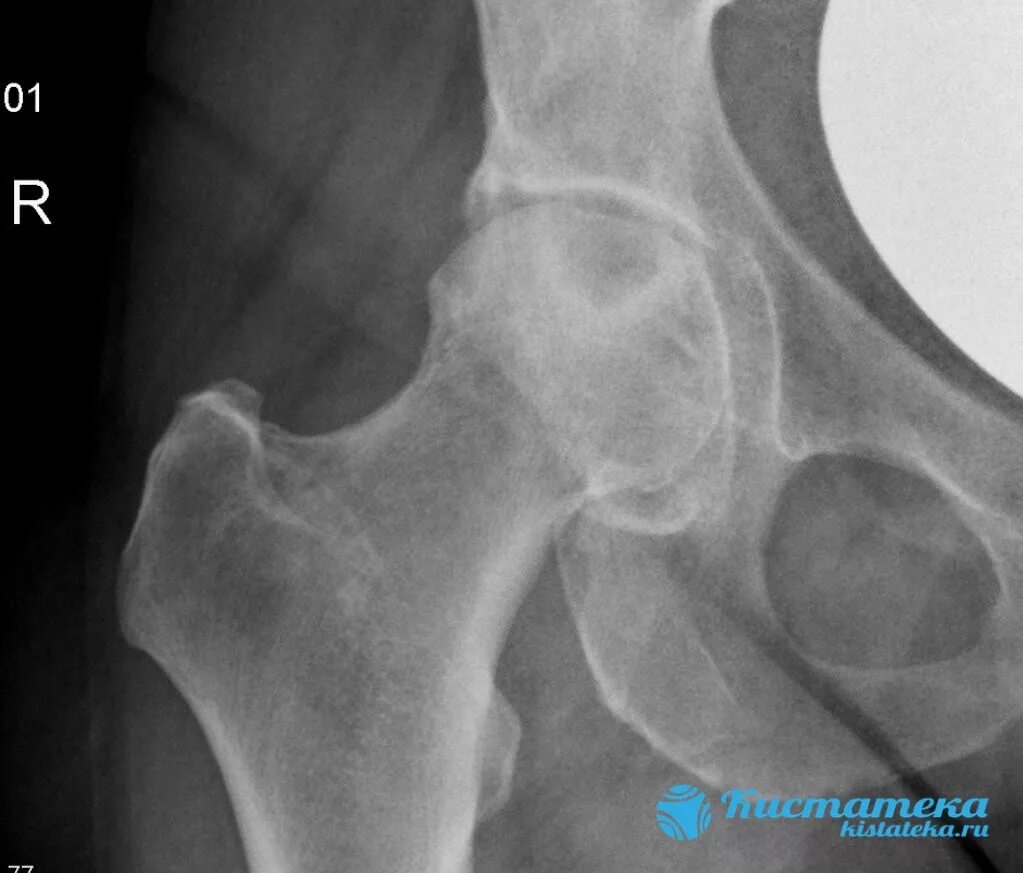

Склероз вертлужной впадины